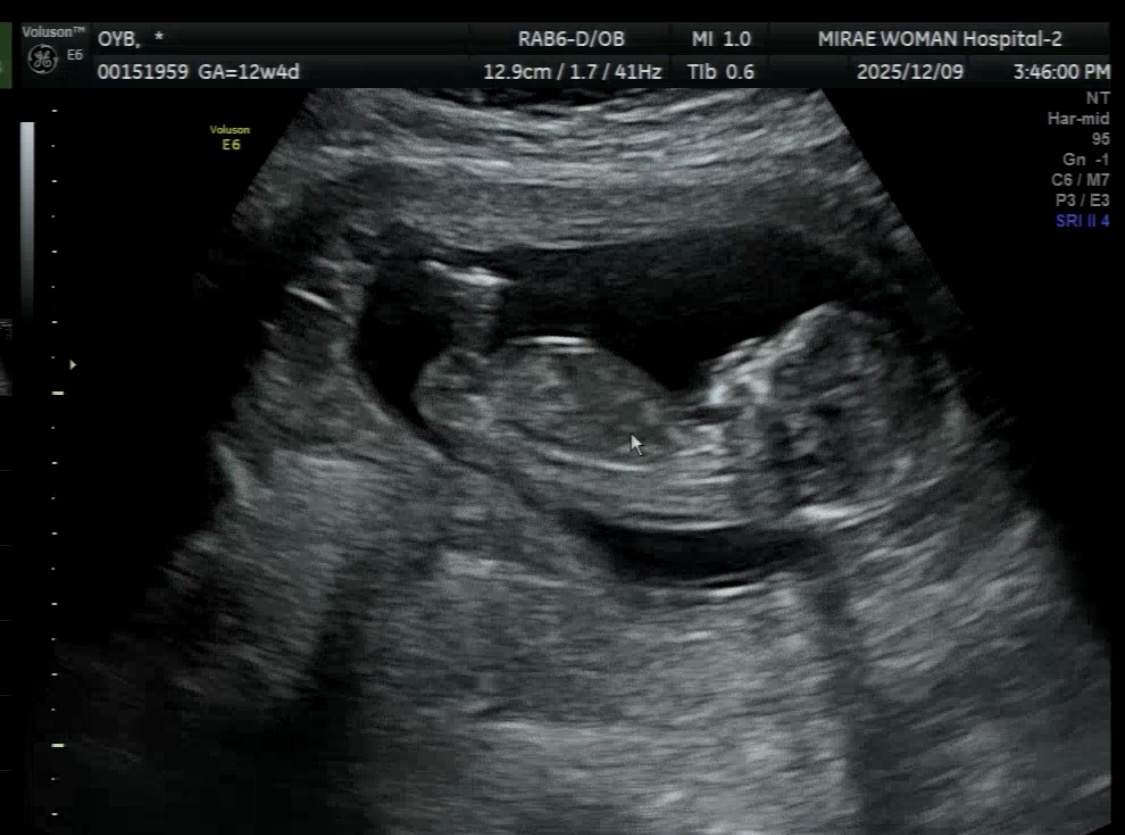

각도법 봐주세용 ㅎㅎ

12주 4일차입니당! 아들같나요? 딸같나요??